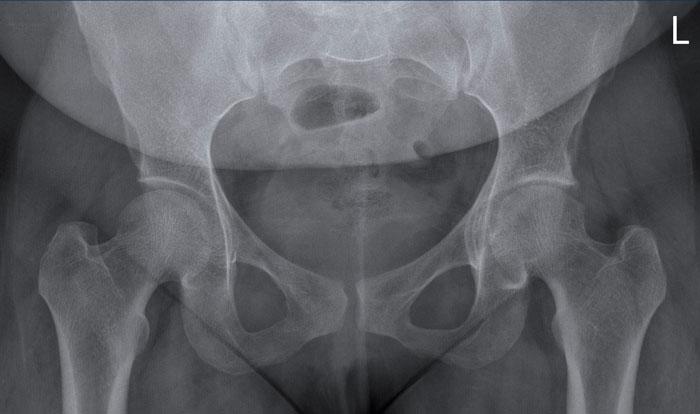

Hình ảnh X-quang khung chậu của bệnh nhân viêm khớp do lao tại khớp háng trái.

Có hẹp khe khớp kín đáo kèm theo xơ cứng dưới sụn tại khớp háng trái.

Các dấu hiệu X-quang này không đặc hiệu và rất có thể là biểu hiện của thoái hóa khớp.

Tiếp tục xem hình ảnh MRI…

Điều bất ngờ với tất cả mọi người là có nhiều ổ áp-xe.

Khi hình thành áp-xe lan rộng như vậy trong khi biểu hiện lâm sàng lại tối thiểu, cần luôn nghĩ đến viêm khớp do lao.

Chẩn đoán viêm khớp do lao được xác lập bằng chọc hút dịch khớp.